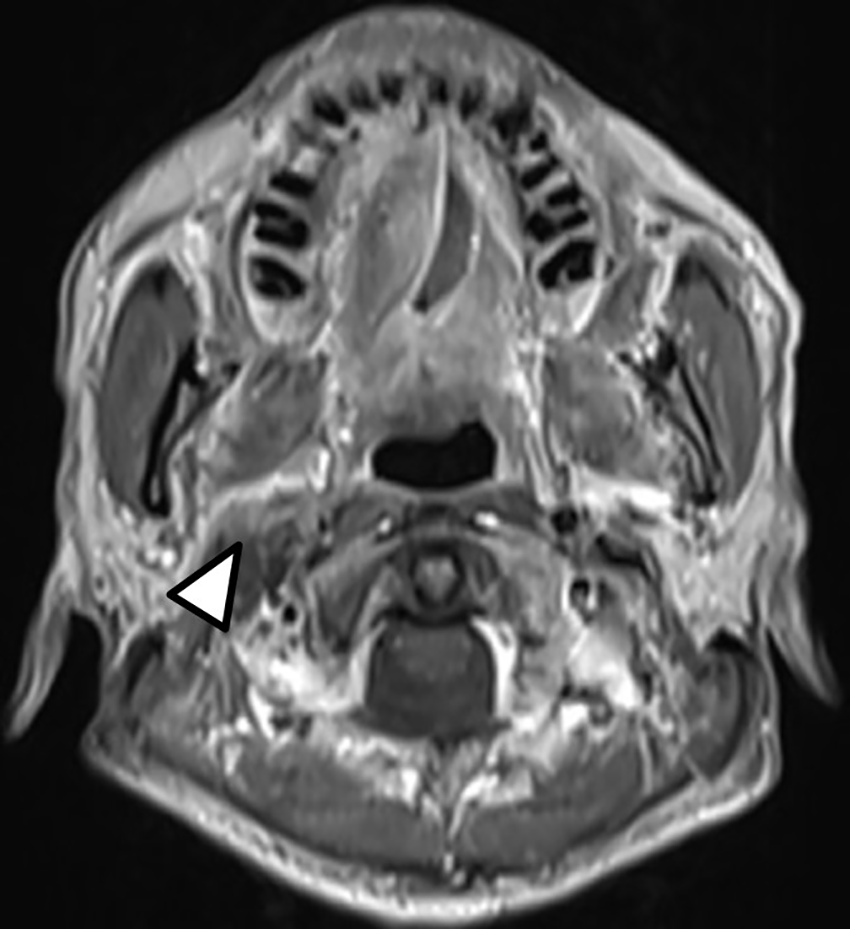

Definitive carboplatin-based CCRT was then initiated one month after biopsy. Conventional fractionated RT to right carotid body tumor and right neck level Ib, II, III (50 Gray [Gy] in 25 fractions [Fx]) followed by right carotid tumor boost (20 Gy in 10 Fx) was delivered via 6MV photons (Figure 2). Weekly carboplatin (area under curve = 2) was administrated concurrently with RT for six cycles. An episode of hospital acquired pneumonia happened during the first month of treatment and subsided after antibiotic treatment. Acute side effects of grade 2 skin reaction, grade 2 oral mucositis, and grade 1 cervical esophagitis were observed during treatment course and were medically controlled without treatment interruption (Figure 3). Post-treatment MRI study revealed decreased main tumor size three months after CCRT (Figure 4). He did not receive adjuvant chemotherapy, and the disease remained controlled one year after the treatment without treatment related late toxicities. In addition, his blood pressure is within normal range and there was no evidence of postural hypotension or episodes of syncope or near syncope. Owing to the absence of symptoms of baroreflex failure, neurophysiology examinations are not indicated for this patient.

Figure 4

Post-treatment T1-weighted head and neck MRI showed decreased size of the right carotid body tumor with slightly anterior displacement of the right parapharyngeal fat (Arrow head).